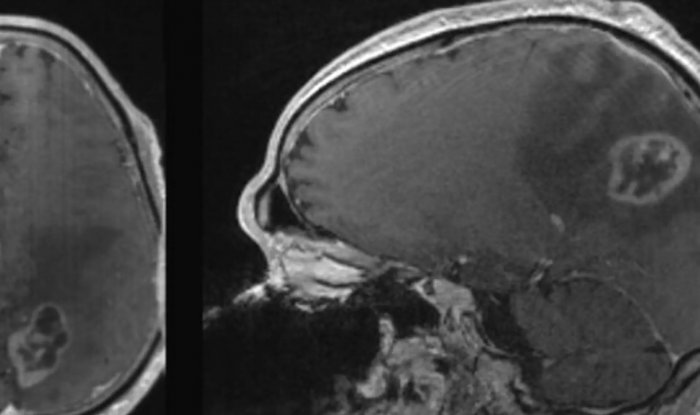

Ученые из Университета Северной Каролины доказали возможность исцеления от онкологических заболеваний при помощи диеты, без применения медикаментов или хирургического вмешательства. Они научились провоцировать ферроптоз — механизм гибели клеток, который связан с содержанием в них железа. Он присущ в первую очередь именно раковым клеткам, таким как глиобластома, смертность от которой достигает 100%, при этом лекарств от нее не существует.